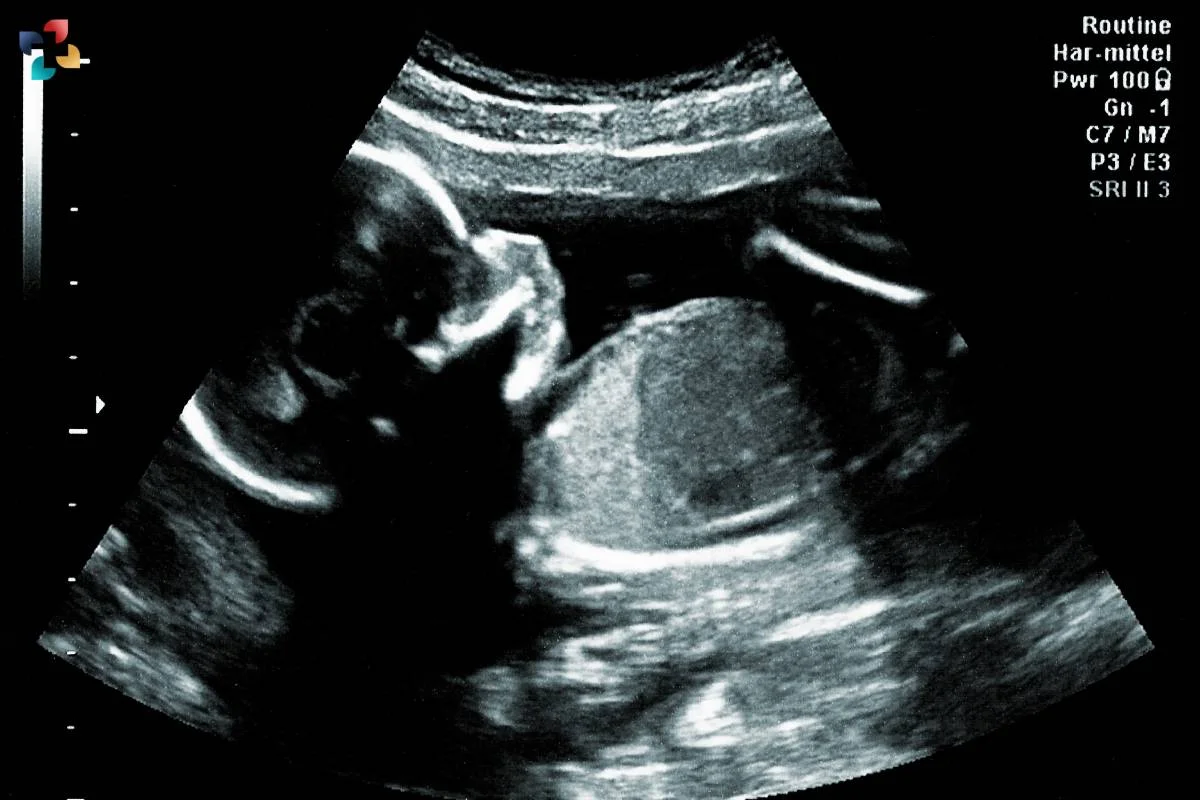

A Biophysical Profile (BPP) ultrasound is a crucial prenatal imaging test that evaluates the well-being of the fetus by assessing various parameters, including fetal movement, muscle tone, breathing activity, and amniotic fluid levels. The ultrasound biophysical profile helps doctors determine if the baby is receiving adequate oxygen and nutrients for healthy development. At Medifyhome, we offer high-quality biophysical profile ultrasound services at NABL-accredited diagnostic centers, ensuring precise and reliable results. The test is non-invasive, painless, and does not use radiation, making it completely safe for both mother and baby. During the scan, the radiologist assigns a score to each fetal activity, with a total score of 8 to 10 indicating a healthy baby, while lower scores may require further monitoring or medical intervention. Schedule the scan with Medifyhome at affordable prices and receive detailed insights of your baby’s well-being.

An Ultrasound Scan for Biophysical Profile (BPP) is a prenatal test that evaluates fetal health and well-being by measuring parameters such as breathing movements, body movements, muscle tone, amniotic fluid volume, and heart rate.